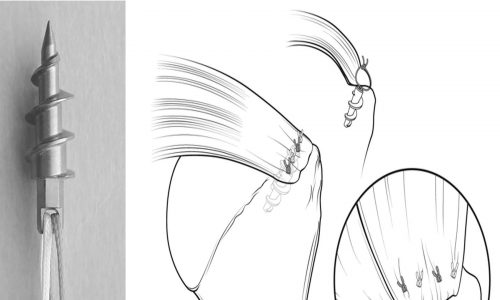

Επί αποτυχίας της συντηρητικής αγωγής ή σε περιπτώσεις νέων ατόμων ή αθλητών έχει θέση η χειρουργική θεραπεία. Αυτή έχει ως στόχο τη συρραφή των τενόντων στην ανατομική τους θέση. Γίνεται με αρθροσκοπικές τεχνικές δηλαδή δια μέσου τριών μικρών οπών στο δέρμα, από τις οποίες εισάγονται κάμερα και ειδικά εργαλεία. Οι τένοντες συρράπτονται με ράμματα τα οποία καθηλώνονται με ειδικές άγκυρες στο οστούν.

Η επέμβαση γίνεται με γενική αναισθησία συνήθως, αλλά υπάρχει και η δυνατότητα περιοχικής αναισθησίας. Ο ασθενής παραμένει στο νοσοκομείο για ένα βράδυ. Στη συνέχεια ακολουθεί πρόγραμμα αποκατάστασης που διαρκεί περίπου τρεις μήνες.